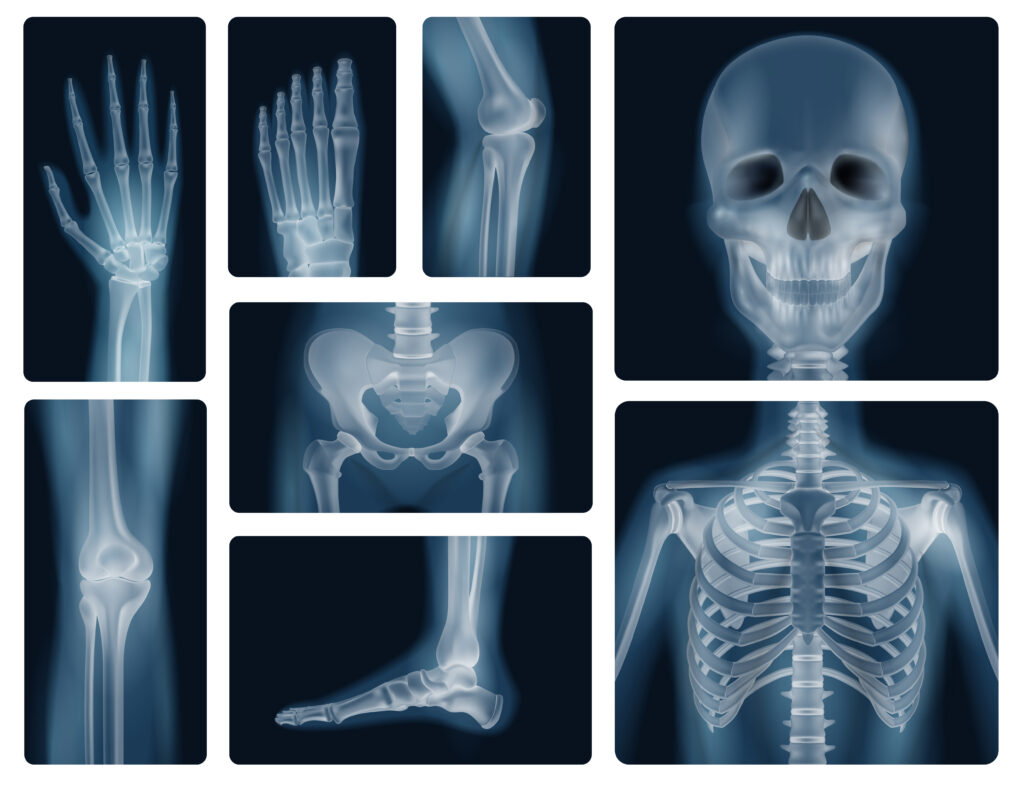

La radiographie est une technique d’imagerie médicale permettant l’obtention de clichés des os ou de différents organes de la zone corporelle à analyser. Le terme « radiographie » regroupe, par ailleurs, l’ensemble des examens basés sur l’utilisation des rayons X. Les rayons X sont des rayonnements ionisants ayant la propriété de pouvoir traverser la matière vivante. Cet examen est totalement indolore. Il ne nécessite ni anesthésie ni hospitalisation. En revanche, compte tenu des risques d’irradiation, il est contre indiqué en cas de grossesse ou d’allaitement.

A quoi sert la radiographie ?

On peut réaliser des radiographies de tout le corps. Elle permet surtout l’étude du squelette et des articulations, des poumons, de l’abdomen, des seins.

Les radiographies sont utiles à votre médecin dans sa démarche diagnostic et afin de réaliser un traitement adapté.

Elle recherche :

Au niveau des os, des fractures, de l’arthrose, des malformations.

Au niveau du poumon, elle dépiste des lésions de tuberculose, d’infections bactériennes ou virales, des tumeurs.

Au niveau de l’abdomen, elles visualisent les calculs présents dans la vésicule ou les reins, des signes d’occlusion ou de perforation digestives.